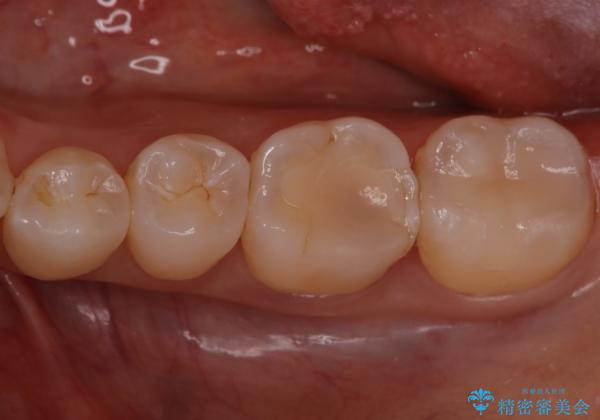

- 銀歯が気になるということで来院された患者様です。

セラミックでの治療を希望されたので治療をいたしました。

銀歯は長い間使用していると隙間ができて、虫歯の原因になります。

そのため適合の良いセラミックをお勧めいたします。